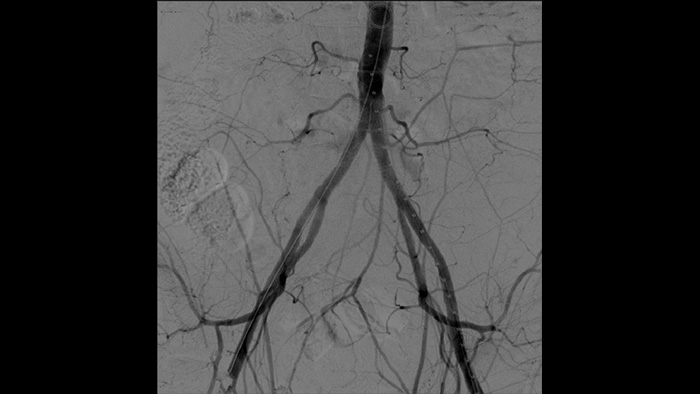

Благодаря Zenition качество изображения DSA значительно улучшилось. Изображение больше не зернистое, а четкое.

Цифровая субтракционная ангиография (DSA) используется в интервенционных сосудистых процедурах для четкой визуализации кровеносных сосудов путем удаления структур, которые могут снижать видимость сосудов. В рамках рентгеноскопии с картой сосудов ранее полученное субтракционное изображение с контрастированием накладывается на полученное рентгеноскопическое изображение в режиме реального времени, что позволяет отслеживать устройство без повторного введения контраста.